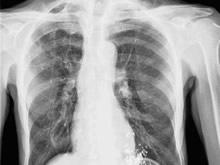

椎管内结核肉芽肿又称椎管内结核瘤、非典型脊椎结核。椎管内结核系指结核性肉芽肿位于在硬膜外或硬膜下,引起脊髓功能障碍,临床特点为渐进性脊髓受压症状。椎管内结核性肉芽肿可见于任何年龄,多见于青壮年。硬膜外肉芽肿比硬膜下肉芽肿多见,两者比例约为10:1。